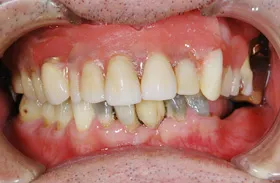

重度の歯槽膿漏のケース

■治療前

■治療後

治療のポイント

上下に入れ歯を入れていましたが、ここ数年しっかりと噛む事がなかった患者様です。何でもおいしく食事ができるようになりたいと希望され、来院されました。

治療法としては、最小限のインプラントの本数で対応ができるように、オールオンフォーを意識した治療法で対応させて頂きました。

| 主訴 | 噛めない |

| 治療方法 | 上顎8本、下顎6本のインプラントを埋入し固定性の入れ歯で治療した |

| 治療期間 | 約1年 |

| 通院回数等 | 20回 |

| 費用 | 上顎4,130,000円 下顎3,630,000円(税込) |

| リスク・副作用 | 治療後に一時的に腫れることがある |